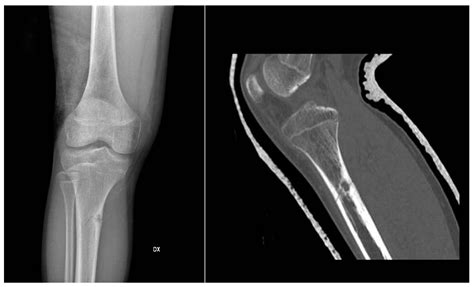

Bony lesions refer to any abnormal growths, defects, or changes in the bone tissue. These lesions can be benign (non-cancerous) or malignant (cancerous) and can occur in any part of the skeletal system. They are often detected through imaging techniques such as X-rays, CT scans, MRI, or bone scans. The characteristics of bony lesions can vary widely, making accurate diagnosis essential for appropriate treatment.

• Imaging Studies: X-rays, CT scans, MRI, and bone scans are commonly used to visualize the lesion and determine its characteristics.